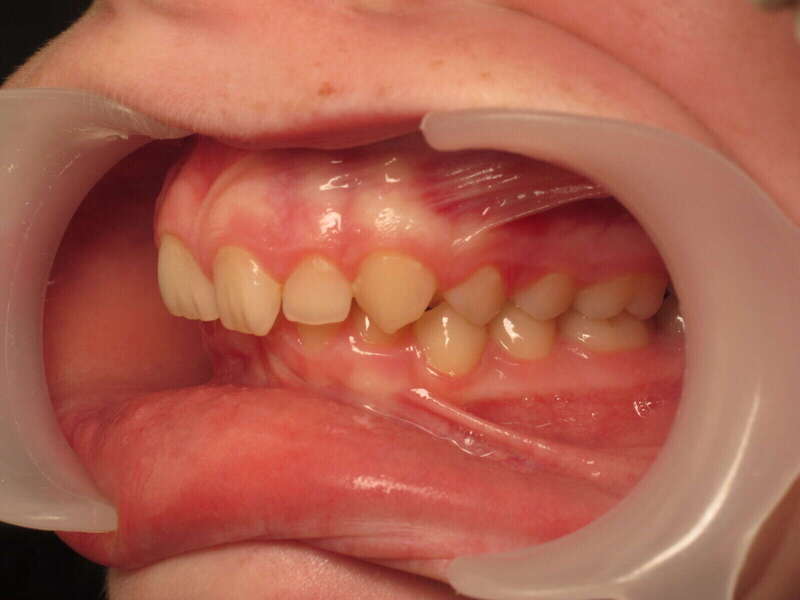

Cas n°1 traité par aligneurs (interception) - enfant

Ce cas d’interception chez un enfant de 8 ans démontre l'efficacité des aligneurs pour corriger des troubles fonctionnels précoces. Le diagnostic présentait des inversions d'articulé provoquant une déviation de la mandibule vers la gauche et un décalage des milieux.

Grâce à une coopération exemplaire et un traitement totalement indolore, l'expansion de l'arcade a permis de recentrer la mâchoire. Cette intervention a littéralement remis la croissance sur les rails, neutralisant le risque d'asymétrie faciale squelettique.